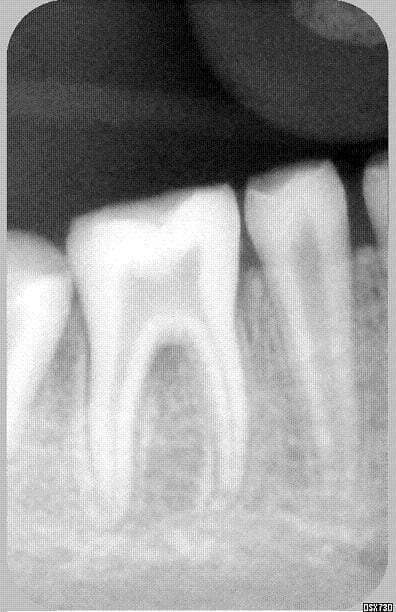

jeune patiente 11ans, je l'ai suivie il y a quelques années, pour les lacteales et sans probleme.

je la revois aujourd'hui, 11ans, et la denture definitive ne dit rien de bon pour son avenir....

as tu fait radios pour juger si il s'agit uniquement d'amelogenese ou s'il s'agit aussi de dentinogenese imparfaite...